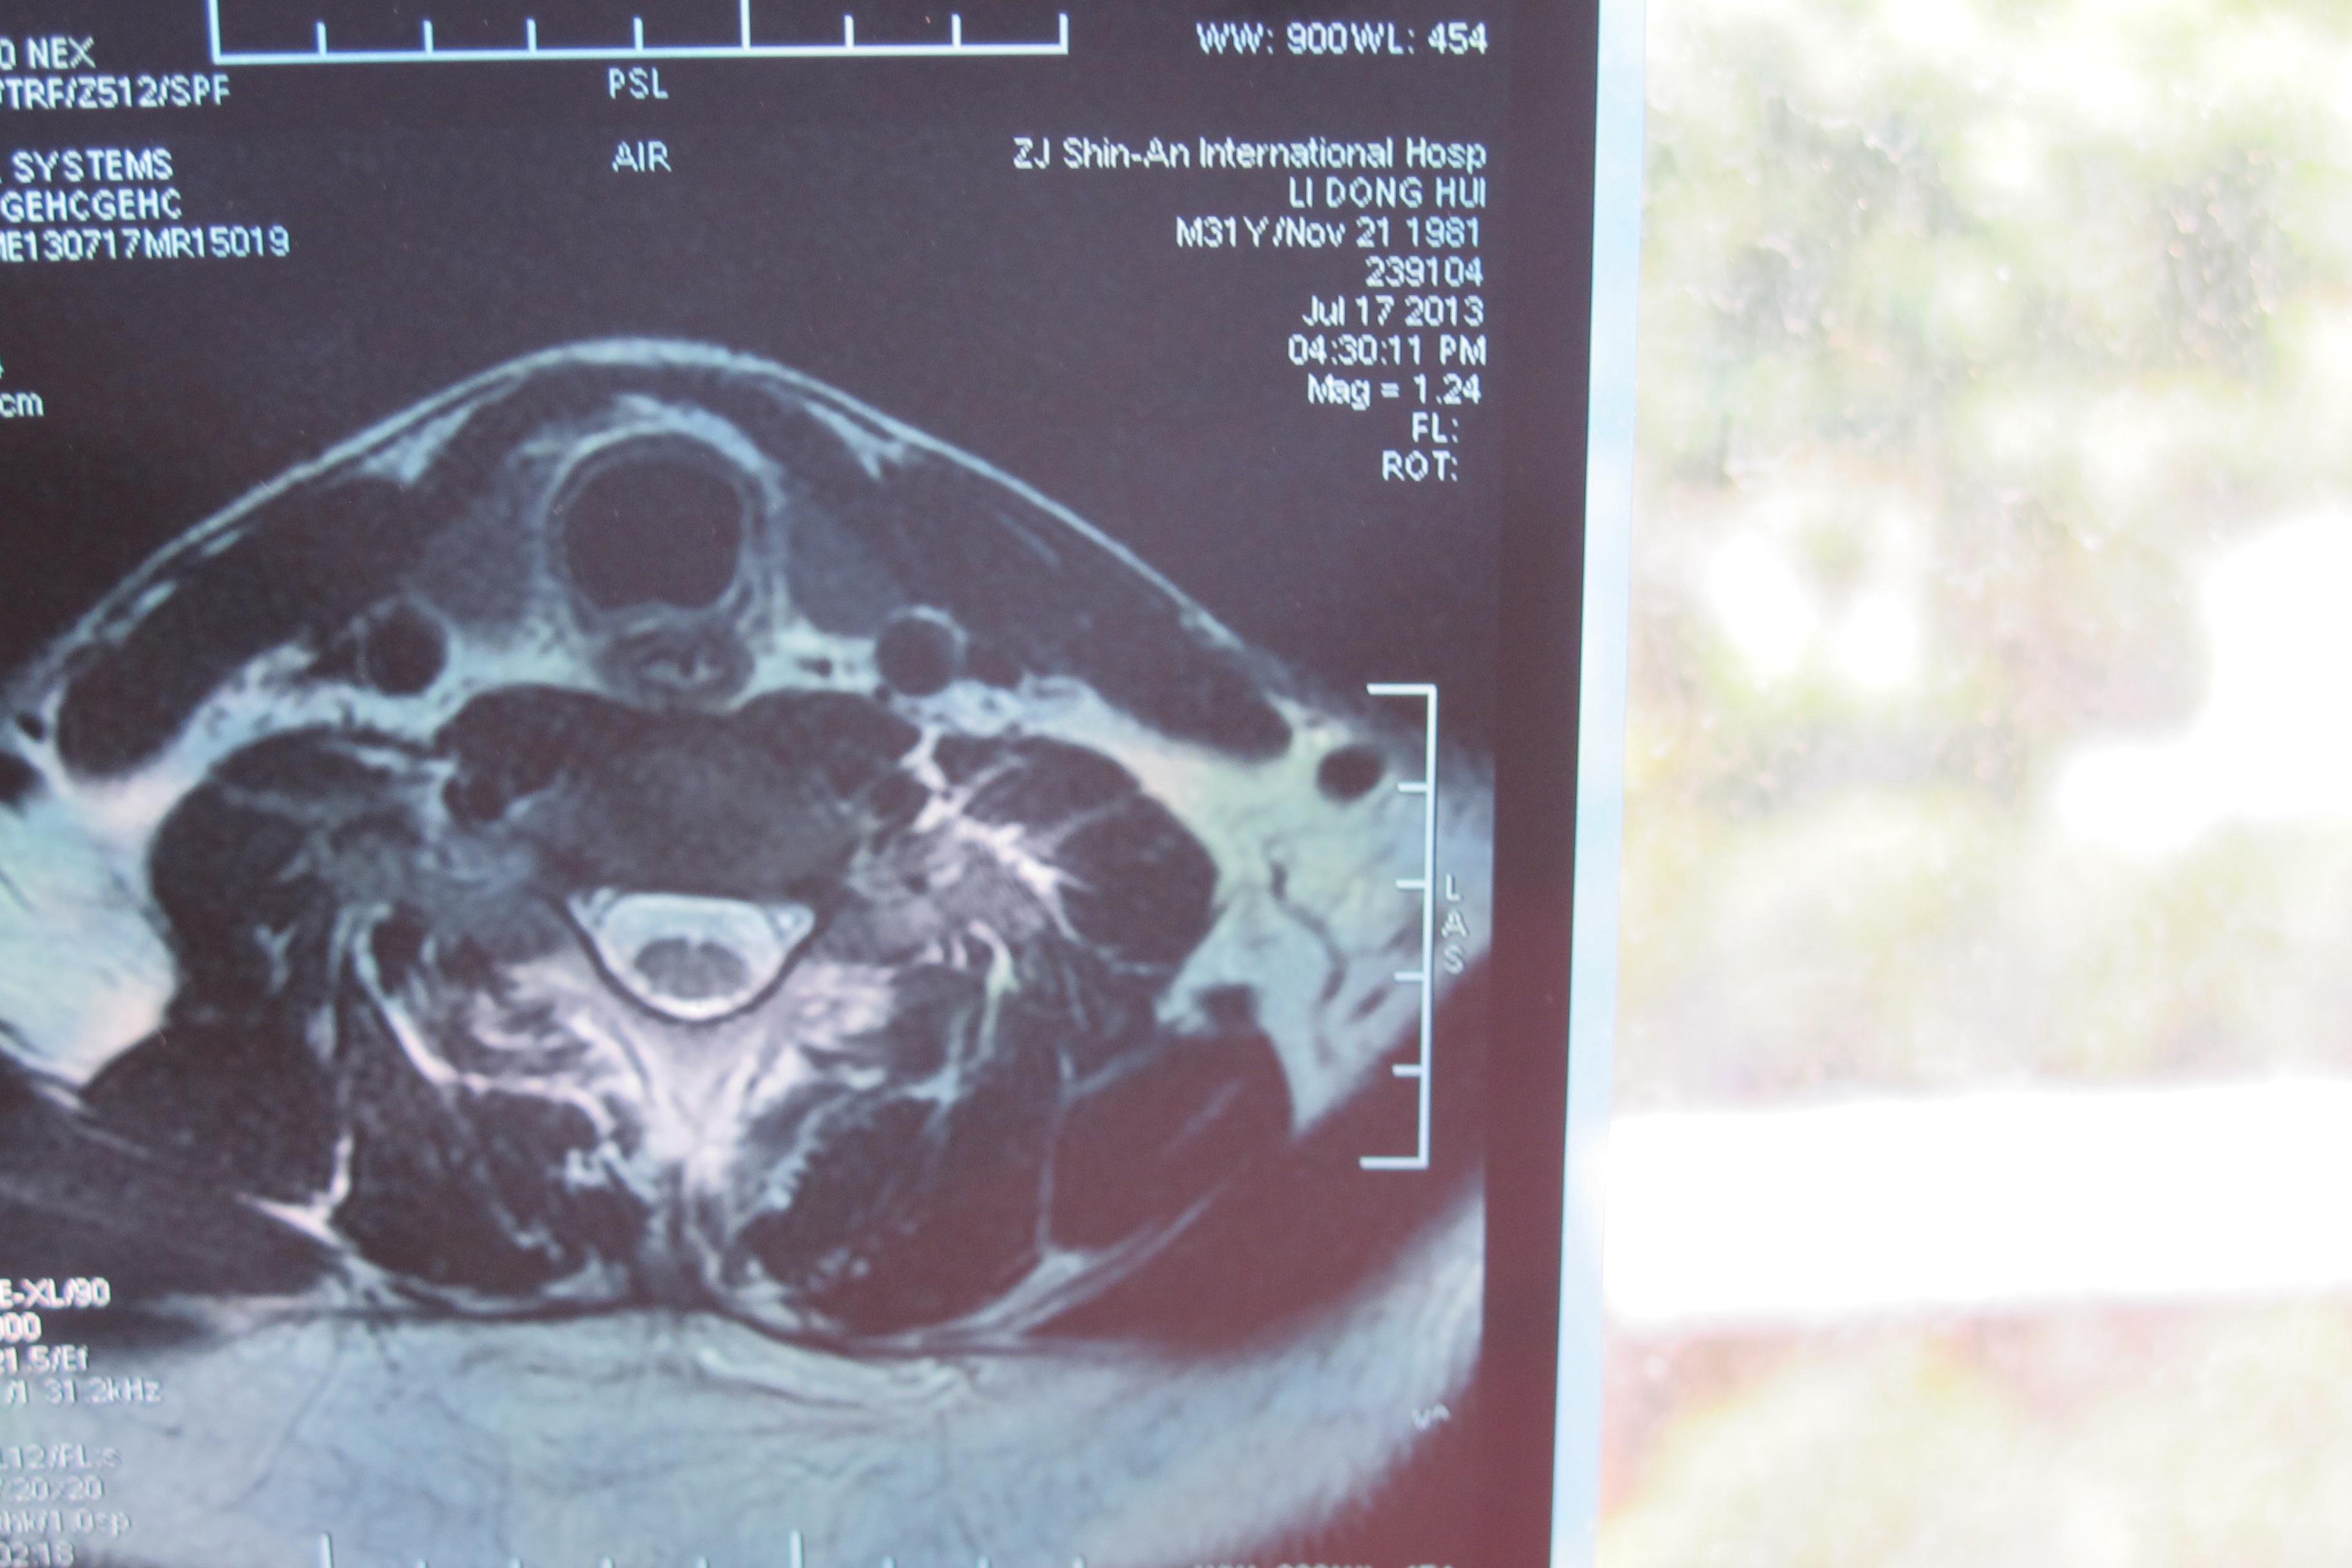

年轻多节段椎间盘突出颈椎病的治疗【1119】 [精华]

图片尺寸3648x2736

颈椎核磁片显示:颈4,5,6,7位颈椎间盘突出!